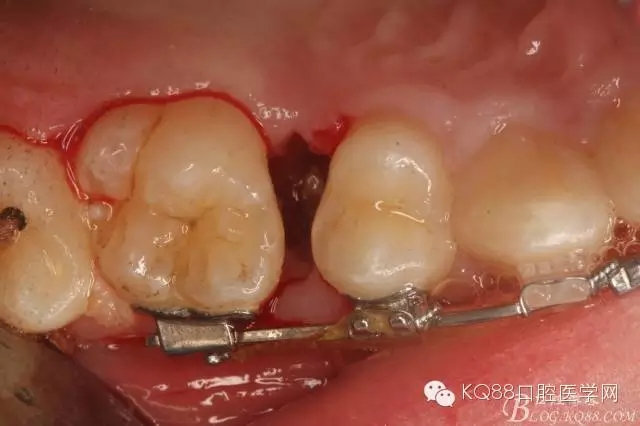

圖8.因16與14合面的間隙僅2mm左右,牙根無法合向脫位,如何考慮15牙根的脫位將是最大問題。高速手機去除牙間隙內(nèi)的覆蓋在15牙根表面的牙齦組織

圖10.去除牙齦組織后。露出15牙根斷面,合面無法脫位